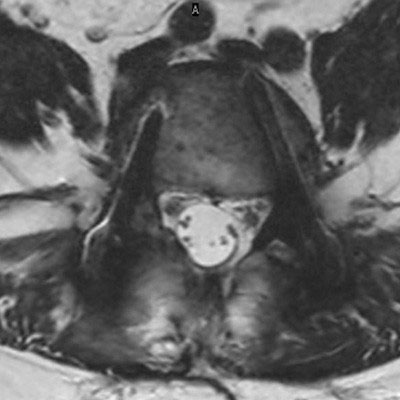

Lumbar Spine with metal implant, routine and fast

Utrecht Medical Center, The Netherlands

**Only for use with MR Safe or MR Conditional Implants by strictly following the Instructions for Use.